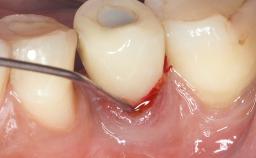

This case describes both a surgical and an anti-infective approach for the management of peri-implantitis, including treatment of the entire dentition to eliminate any deep periodontal pockets that could serve as reservoirs for bacterial re-colonization at the implant site. A 65-year-old female patient was referred to the periodontist in 2013 for assessment and management of an infection at implant 12. On examination, probing depths at implant 12 were 11 mm with suppuration and bleeding on probing.